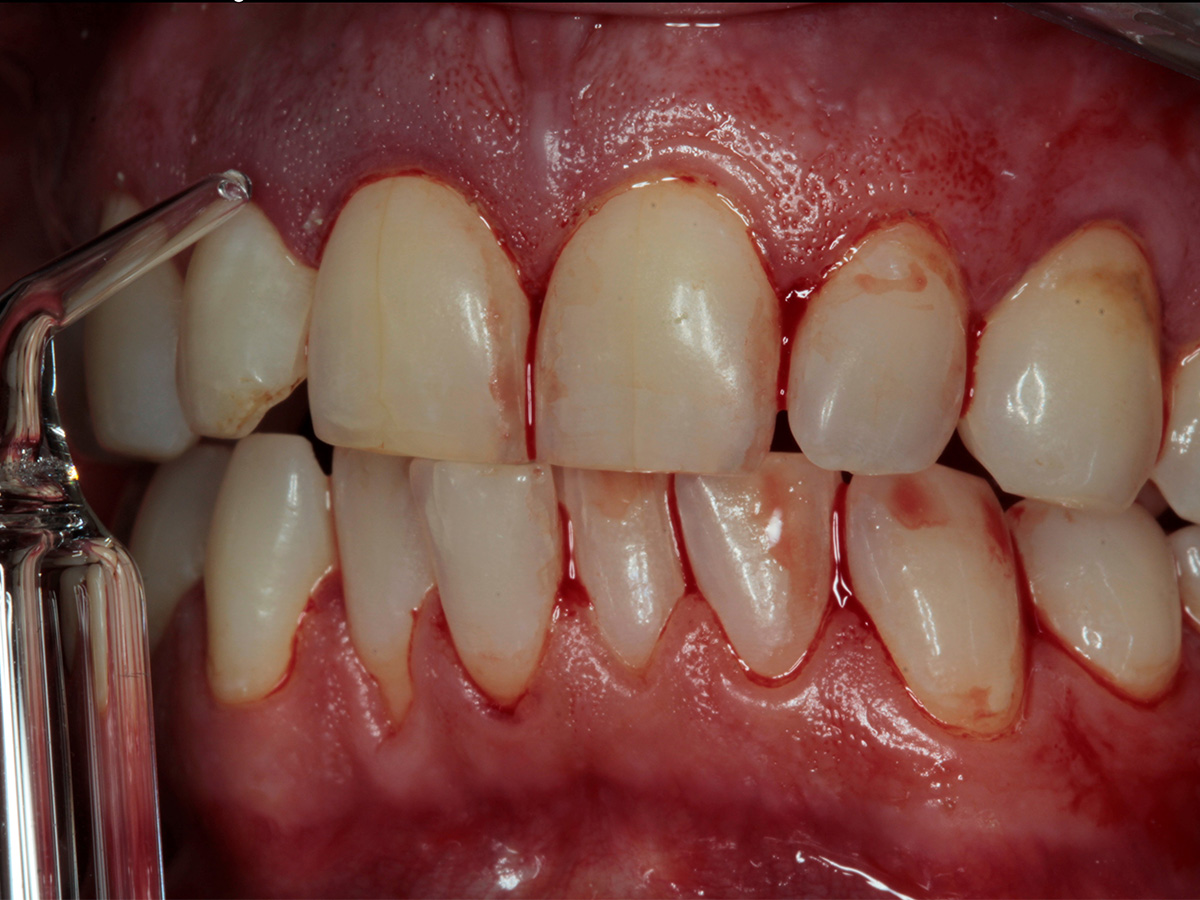

In diesem Workshop erhalten Sie umfassendes Wissen für die Behandlung von Parodontitis-Patientenen. Zunächst führt Sie Yvonne Gebhardt durch moderne subgingivale Behandlungskonzepte – das Herzstück der PA-Therapie. Anschließend erklärt Ihnen Sonja Steinert die faszinierenden Zusammenhänge des Knochenstoffwechsels: Wie Entzündungen den Knochenabbau fördern und wie Sie mit gezielter Therapie und Vitamin D gegensteuern können.

• Parodontale Krankheitsbilder erkennen